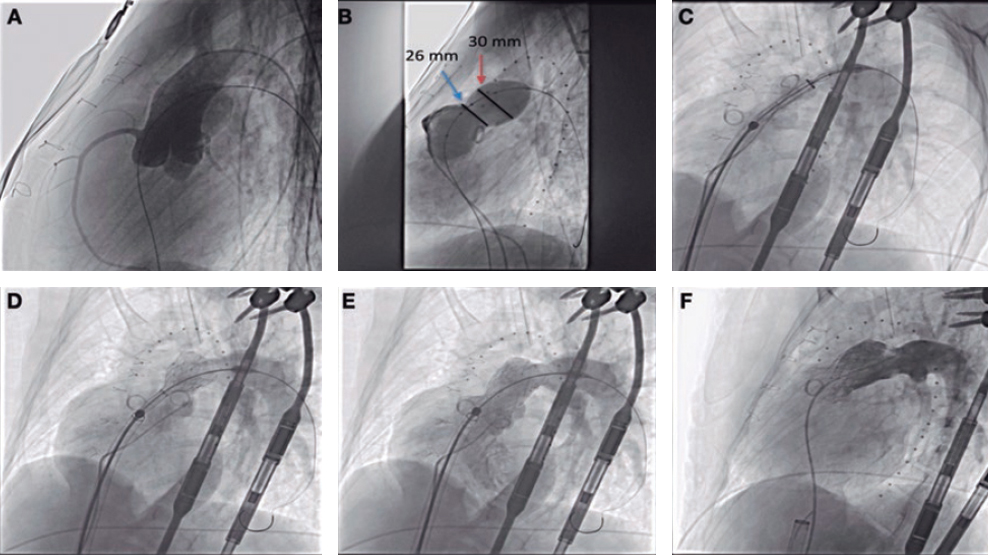

We should emphasize that the use of mechanical circulatory assist devices in the setting of STEMI-related cardiogenic shock is not recommended systematically (evidence IIbC) since, to this day, we still have not seen any improvements in the short or long-term mortality rate.2 However, its use may be an option on a per-patient basis in to achieve hemodynamical stability, guarantee the proper perfusion of vital organs or as bridging therapy for the recovery of myocardial function.

Given the presence of complete atrioventricular block and severe hypotension, in our case we considered implanting the Impella CP device (AbioMed, Danvers, Massachusetts, United States), which was the device that provided the highest utility since it does not require arterial pulse or an electrocardiographic registry to operate; however, performing a transthoracic echocardiography prior to the implantation of the device could have been decisive for diagnostic purposes and to re-think what was the best therapeutic strategy to use since, probably, the clinical situation of the patient was not only due to the STEMI, but also to the obstructive effect of the mass and the systemic embolization that may have exacerbated after the implantation of the device.